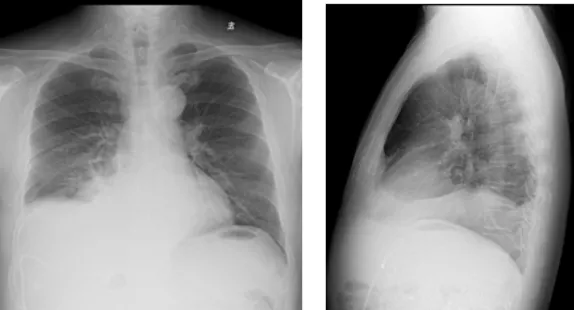

影像學檢查結果

右肺炎癥不能排除,請結合臨床。右側少量胸腔積液